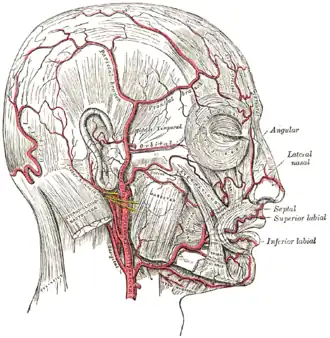

The arteries of the face and scalp

The arteries of the face and scalp